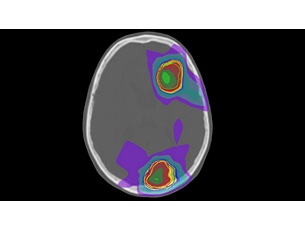

With its excellent soft-tissue contrast, MRI offers excellent visualization of tumor boundaries and proximity to nearby critical structures – a key factor for more confident delineation and improved treatment plans. What’s more, MRI’s advanced imaging capabilities provide you with a ‘toolbox’ to design personalize treatment options for each patient. - Be confident in image quality

With its excellent soft-tissue contrast, MRI offers excellent visualization of tumor boundaries and proximity to nearby critical structures – a key factor for more confident delineation and improved treatment plans. What’s more, MRI’s advanced imaging capabilities provide you with a ‘toolbox’ to design personalize treatment options for each patient. - Be confident in image quality

MRCAT Brain clinical application allows the use of MRI as the primary imaging modality for radiotherapy planning of primary and metastatic tumors in the brain without the need for CT. Detailed anatomical information for contouring and attenuation maps for dose calculations are both obtained from a single, submillimeter resolution 3D T1W mDIXON MR sequence. Artificial Intelligence (AI) is used for fast computation of continuous Hounsfield units directly on the MR console.